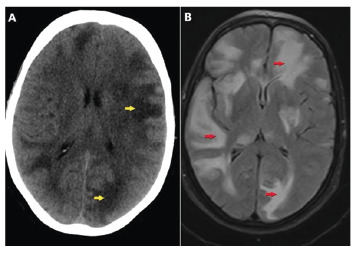

颅内结核瘤伴结核性脑膜炎。

Intracranial Tuberculomas Associated with Tuberculous Meningitis.